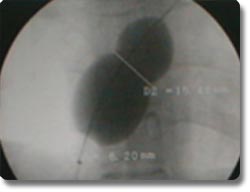

动脉导管未闭、房间隔缺损为先天性心脏发育缺陷,分别形成主动脉、肺动脉间及左右心房间的异常通道,传统治疗方式为外科开胸手术治疗。我科与国外同步开展了非手术经皮动脉导管封堵术及房间隔封堵术,用介入治疗方式矫正异常通道,手术时间30分钟左右,术后2天病员即可康复出院,疗效与外科开胸手术相同。 |